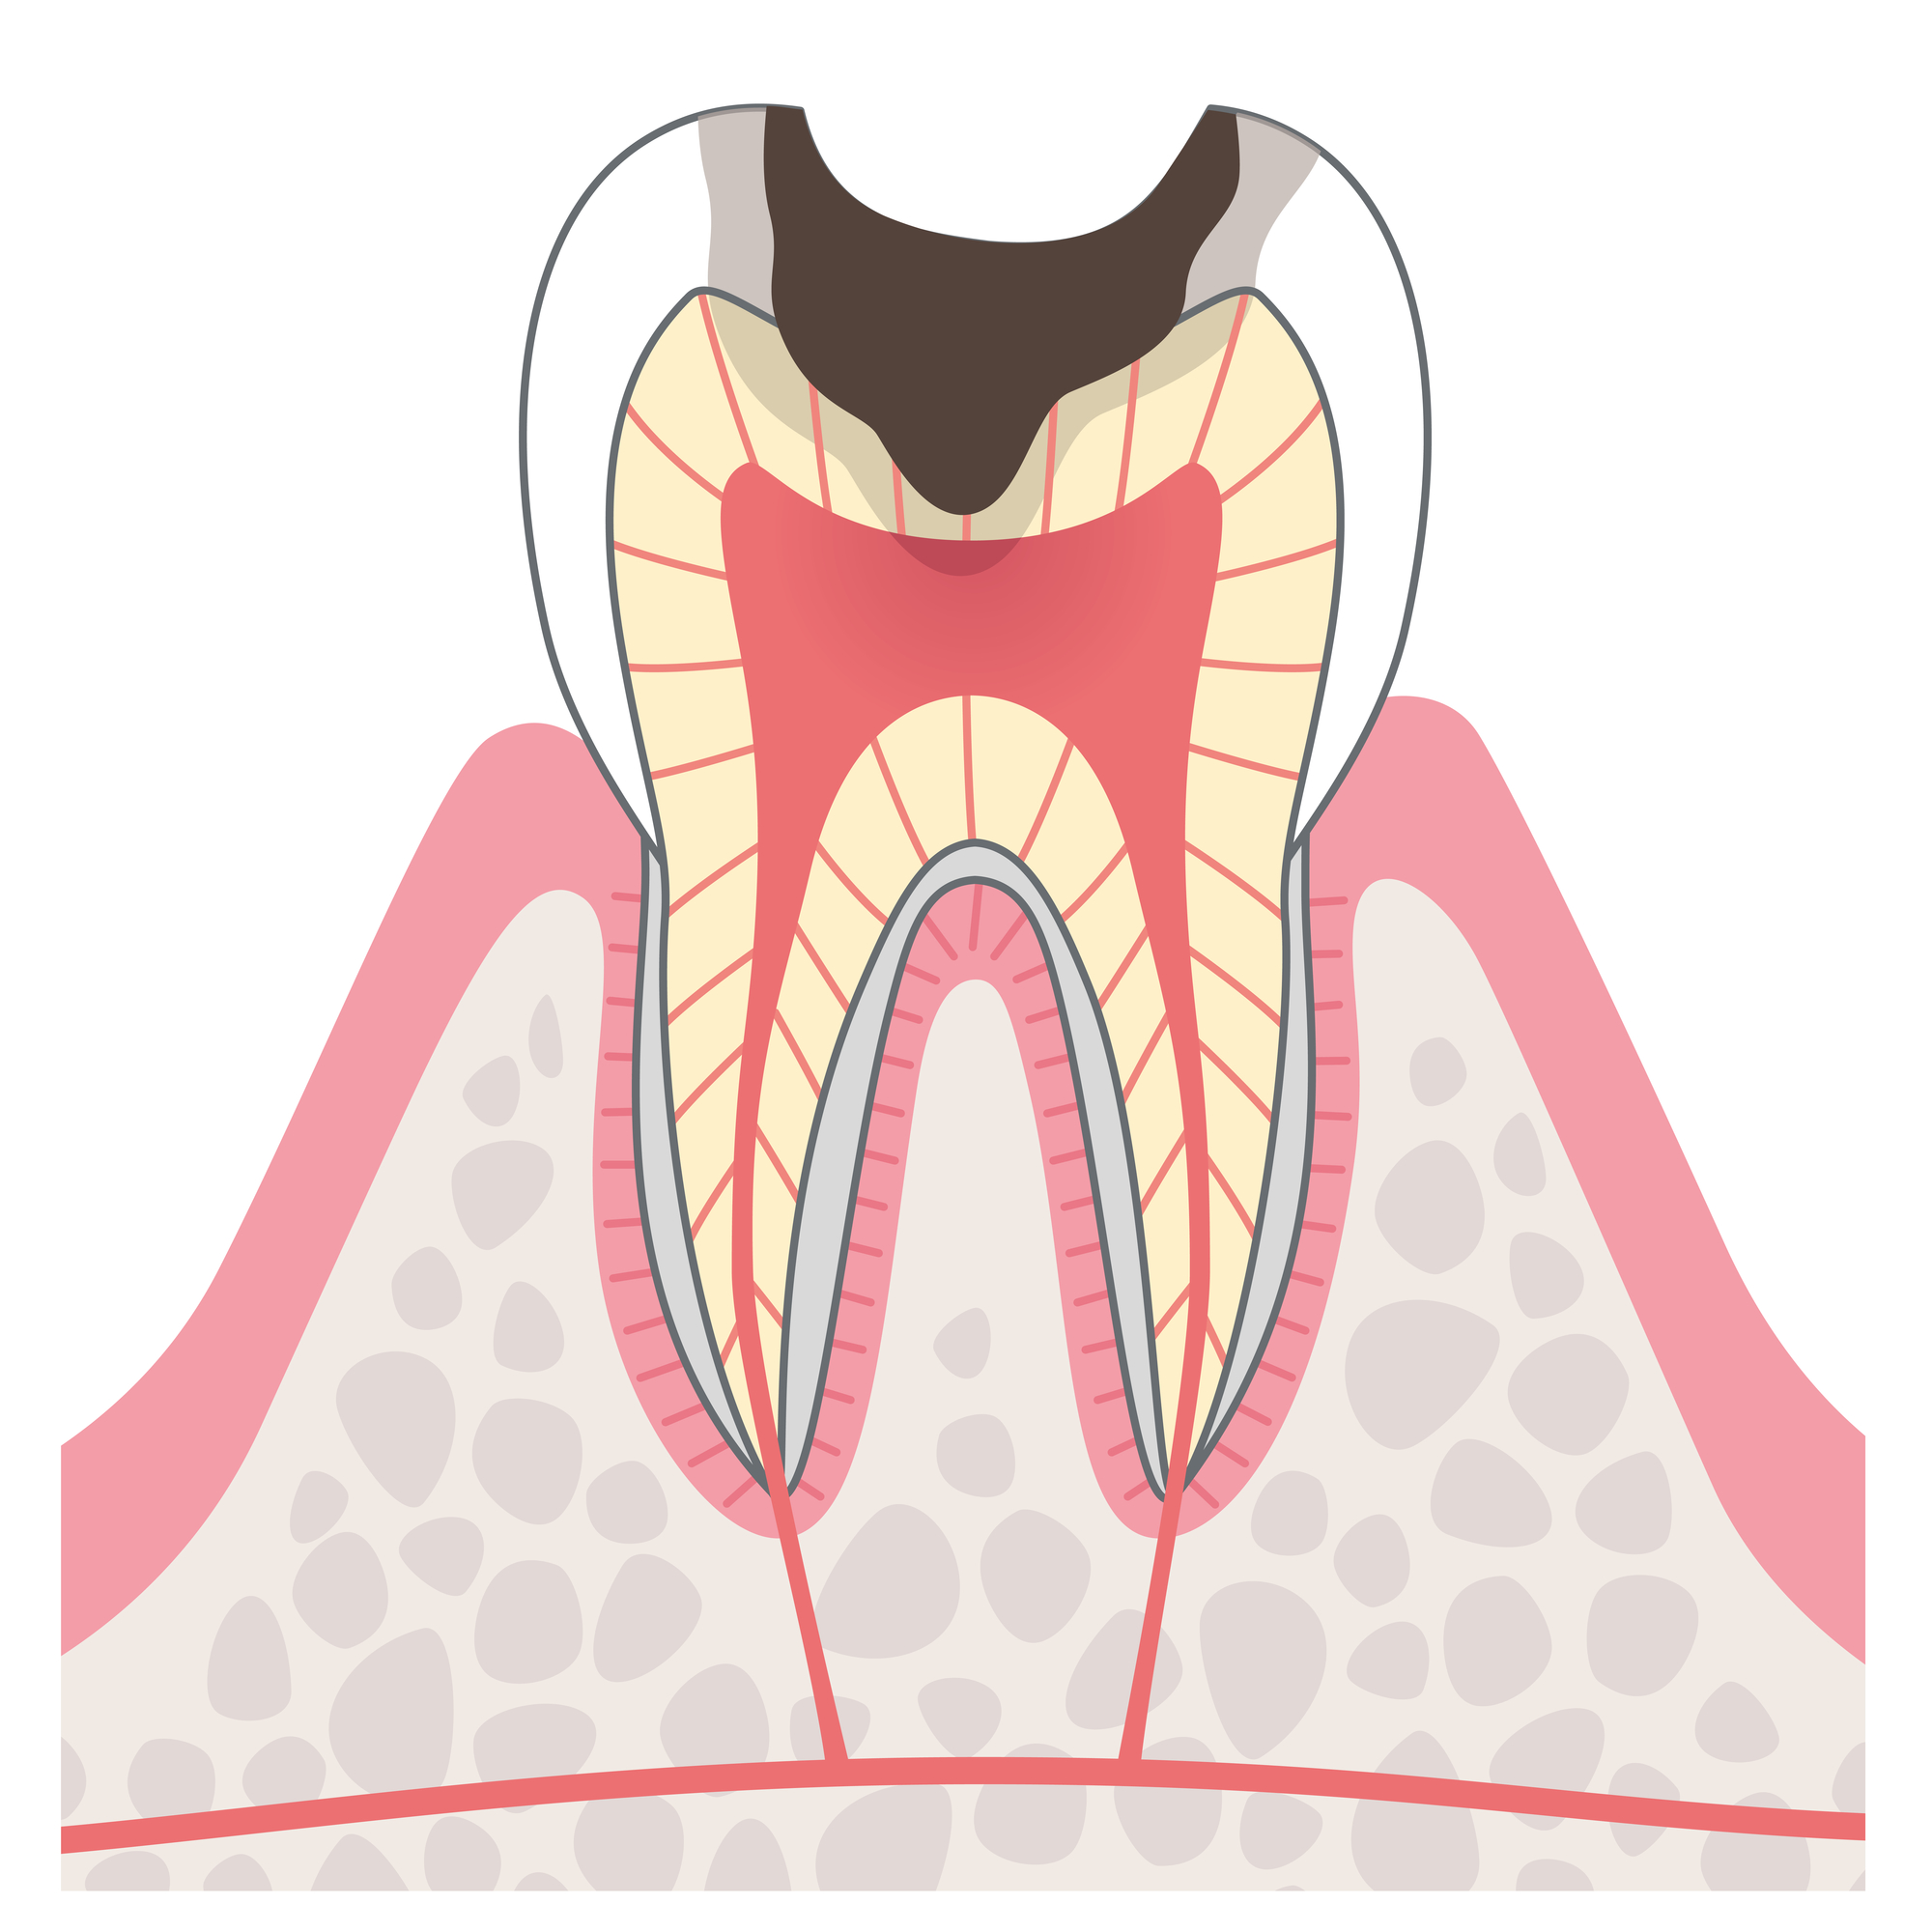

C3

C3は、むし歯が神経にまで達しています。痛みが強くなり、膿が出たり、腫れたりします。

治療方法

- 根管治療